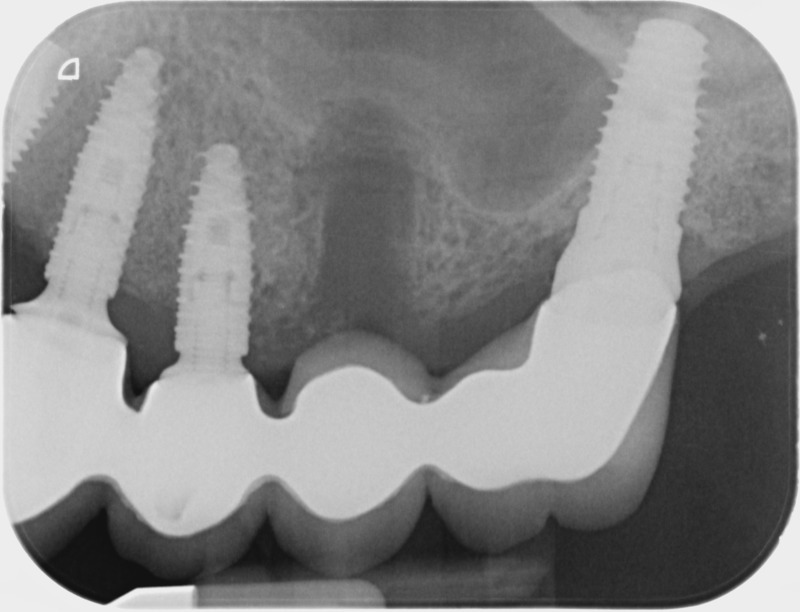

• Couronnes sur implants : Lorsqu’un implant est posé en remplacement des racines d’une dent, il est conçu pour recevoir d’abord un pilier vissé puis une couronne céramique. Le couple couronne - implant se substitue à la dent manquante pour en assurer les mêmes fonctions. Nous pouvons également adapter un bridge sur plusieurs implants dans le cas d’un édentement plus important.